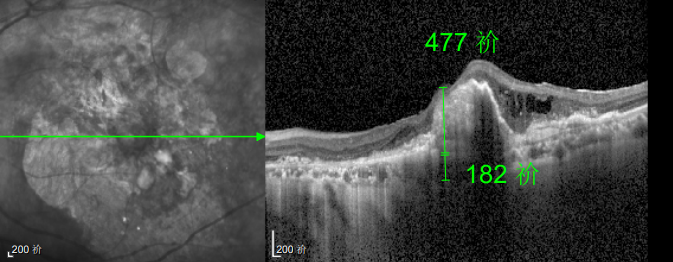

然而好景不长,半年后林婆婆的左眼视力突然骤降,甚至连眼前的人影都难以看清。但她仍抱有侥幸心理,觉得 “再打一针就能好”,恰逢春节临近,便把复查的事一推再推,又延误了3个多月才匆匆赶回医院,可检查结果却给了她沉重一击:由于病情延误,持续的积液已造成黄斑的不可逆损坏,即便后续恢复治疗,也难以回到理想水平。“当时真是肠子都悔青了!”回忆起这段经历,林婆婆至今仍难掩懊悔。

幸运的是,三年后的一次例行复查中,医生通过眼底监测及时发现林婆婆的右眼眼底病变问题,确诊为湿性老年性黄斑变性。得益于定期筛查的及时性,王晓波主任第一时间为她启动治疗,最终成功将右眼矫正视力稳定在0.8左右。